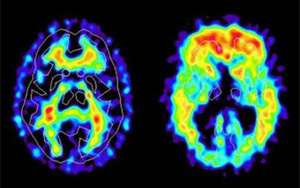

新冠帶來新的“醫(yī)療壓力”:阿爾茨海默病的風險飆升50%-80%

研究發(fā)現(xiàn)感染新冠病毒的老年人患阿爾茨海默病的風險因素增加了50%-80%。